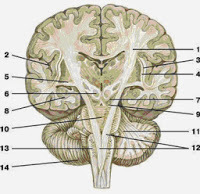

Внутренняя сонная артерия (a. carotis interna) кровоснабжает орган зрения и головной мозг. Выделяют шейную, каменистую, пещеристую и мозговую части (рис. 395).

Шейная часть располагается между глоткой и внутренней яремной веной и не отдает на шее ветвей. Ближе к основанию черепа между внутренней сонной артерией и внутренней яремной веной располагаются языкоглоточный, блуждающий, добавочный и подъязычный нервы. Ниже языкоглоточный и подъязычный нервы пересекают внутреннюю сонную артерию спереди, направляясь вниз и вперед. Блуждающий нерв идет вдоль внутренней сонной артерии.

Кзади от внутренней сонной артерии находятся верхний гортанный нерв и верхний шейный узел симпатического ствола. Каменистая часть внутренней сонной артерии проходит в сонном канале пирамиды височной кости, где от артерии в барабанную полость через сонно-барабанные канальцы уходят две-три тонкие сонно-барабанные артерии (aa. caroticotympanicae).

Далее внутренняя сонная артерия через внутреннее отверстие сонного канала входит в полость черепа, ложится в сонную борозду, где проходит в пещеристом синусе (пещеристая часть), окруженная симпатическим нервом, латеральнее от нее лежат глазодвигательный, добавочный, отводящий и глазной нервы (рис. 396). Возле переднего наклоненного отростка клиновидной кости начинается мозговая часть внутренней сонной артерии.

Здесь она делает изгиб и отдает глазную артерию, прободает твердую мозговую оболочку, проходит между зрительным и глазодвигательным нервами, направляясь к веществу мозга, где разделяется на свои конечные ветви — переднюю и среднюю мозговые артерии.

Глазная артерия (a. ophthalmica) идет в глазницу через зрительный канал рядом со зрительным нервом и отдает тонкие ветви к глазному яблоку и к вспомогательным органам глаза. Слезная артерия (a. lacrimalis) идет к слезной железе, короткие и длинные задние ресничные артерии

Рис. 394.Конечные ветви верхнечелюстной артерии в крылонебной ямке. Артерии латеральной стенки полости носа и твердого неба. Сагиттальный распил головы. Вид с медиальной стороны. Большой небный канал вскрыт.

1 — передняя решетчатая артерия, 2 — задняя решетчатая артерия, 3 — верхняя латеральная артерия носа, 4 — верхняя носовая раковина, 5 — клиновидная пазуха, 6 — задняя артерия перегородки носа, 7 — клиновидно-небная артерия, 8 — артерия крыловидного канала, 9 — нисходящая небная артерия, 10 — глоточная миндалина, 11 — глоточное отверстие слуховой трубы, 12 — малая небная артерия, 13 — большая небная артерия, 14 — нижняя носовая раковина, 15 — верхняя губа, 16 — задняя латеральная артерия носа, 17 — передняя латеральная артерия носа, 18 — средняя носовая раковина, 19 — передняя менингеальная артерия, 20 — лобная пазуха.

Рис. 395.Внутренняя сонная артерия и ее положение в сонном канале. Сагиттальный распил головы. Вид с медиальной стороны. Схема.

1 — наружная сонная артерия, 2 — верхняя щитовидная артерия, 3 — язычная артерия, 4 — лицевая артерия, 5 — восходящая небная артерия, 6 — нижняя альвеолярная артерия, 7 — верхнечелюстная артерия, 8 — нисходящая небная артерия, 9 — средняя менингеальная артерия, 10 — задние носовые латеральные артерии, 11 — передняя решетчатая артерия, 12 — ветви задней решетчатой артерии, 13 — лобная ветвь средней менингеальной артерии, 14 — внутренняя сонная артерия, 15 — теменная ветвь средней менингеальной артерии, 16 — менингеальная ветвь, 17 — поверхностная височная артерия, 18 — восходящая глоточная артерия, 19 — задняя ушная артерия, 20 — затылочная артерия, 21 — внутренняя сонная артерия, 22 — общая сонная артерия.

Рис. 396.Глазная артерия и ее ветви. Вид сверху. Верхняя стенка глазницы удалена.

1 — глазной нерв, 2 — глазная артерия, 3 — зрительный нерв, 4 — верхняя глазная вена, 5 — латеральная прямая мышца, 6 — нижняя прямая мышца, 7 — слезная артерия, 8 — слезная вена, 9 — вортикозная вена, 10 — верхняя прямая мышца, 11 — слезная железа, 12 — эписклеральные вены, 13 — глазное ябло- ко, 14 — сухожилие верхней косой мышцы глазного яблока, 15 — надглазничная вена, 16 -лобная чешуя, 17 — блок, 18 — надглазничная артерия, 19 — задние ресничные артерия и вена, 20 — передние решетчатые артерия и вена, 21 — верхняя косая мышца, 22 — петушиный гребень, 23 — передняя менингеальная артерия, 24 — решетчатые ячейки, 25 — задние решетчатые артерия и вена, 26 — зрительный нерв, 27 — внутренняя сонная артерия, 28 — бугорок седла, 29 — передний межпе- щеристый синус, 30 — пещеристый синус, 31 — диафрагма седла, 32 — задний межпещеристый синус, 33 — спинка седла, 34 — внутренняя сонная артерия (пещеристая часть), 35 — глазодвигательный нерв, 36 — блоковый нерв, 37 — тройничный узел, 38 — нижнечелюстной нерв, 39 — верхнечелюстной нерв.